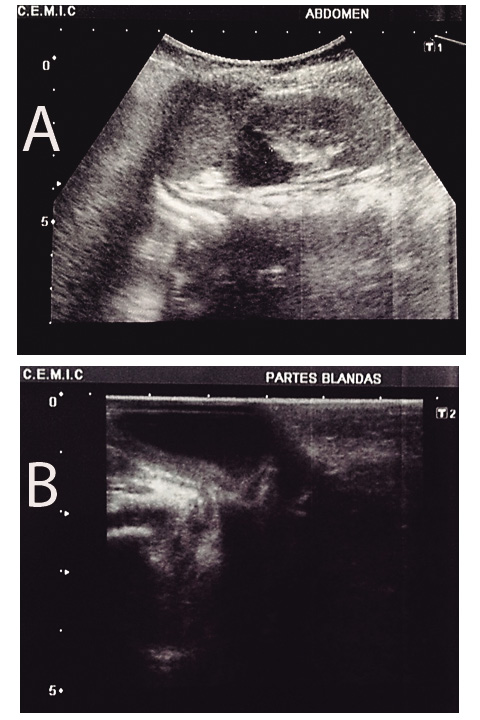

Laboratorio: Hb 11,8 g/l; Htc 34,3 %; GB 16,530 mm3, N 66%, L 24%; plaquetas 401 000 mm3, KPTT 40”. Ecografía renal: riñón derecho de forma y tamaño normal, sin hidronefrosis. Riñón izquierdo de forma y tamaño normal, con una imagen líquida parahiliar de 14 mm, compatible con doble sistema colector incompleto con dilatación del segmento proximal (Figura 2A). Ecografía vesical: imagen con contenido líquido denso de 22 x 19 mm, comunicada con estructuras pelvianas y relacionada con el sistema urinario, compatible con ureterocele (Figura 2B).

Figura 2 A. Ecografía renal: doble sistema colector incompleto con dilatación del segmento proximal

Figura 2 B. Ecografía vesical: imagen con contenido líquido denso de 22 x 19 mm, comunicada con estructuras pelvianas y relacionada con el sistema urinario, compatible con ureterocele.